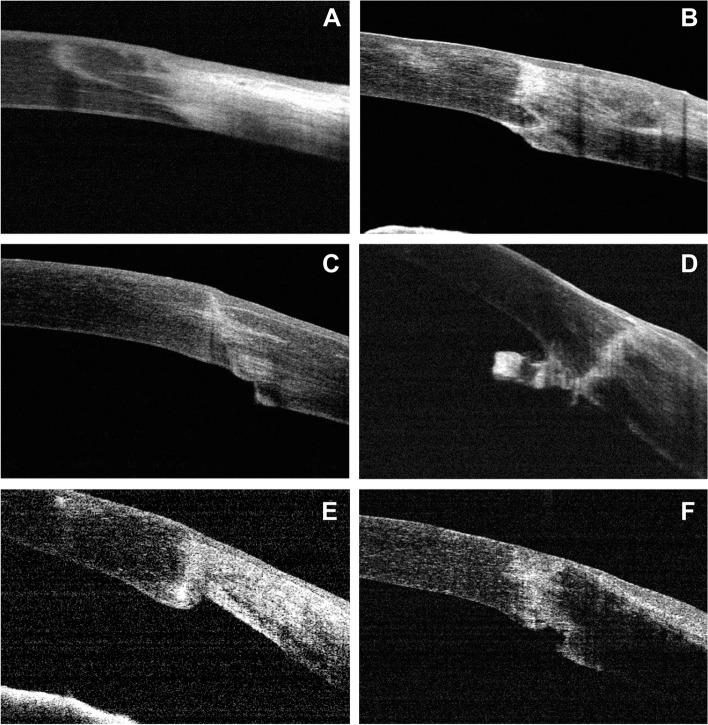

To evaluate anterior synechiae after penetrating keratoplasty (PK) in patients with Peters' anomaly using anterior segment optical coherence tomography (OCT).

A retrospective cross-sectional study was performed. The medical records of patients diagnosed with Peters' anomaly who underwent PK between 2013 and 2018 were reviewed. In addition to basic ophthalmic examinations, images of anterior segment structures were obtained via spectral-domain OCT at baseline and during the postoperative follow-up period. The profiles of postoperative anterior synechiae and multiple potential risk factors were analyzed.

Seventy-one eyes of 58 patients, aged 5 to 23 months, were included. Various extent of postoperative anterior synechiae was observed in 59 eyes (83.1%). OCT findings revealed graft-host junction synechiae, peripheral anterior synechiae, and a combination of both. Disease severity and malposition of the internal graft-host junction were significantly associated with the formation of postoperative synechiae. Multivariate regression analysis found that preexisting iridocorneal adhesion [odds ratio (OR) = 16.639, 95% confidence interval (CI) 1.494-185.294, p = 0.022] was positively correlated with postoperative anterior synechiae, whereas anterior chamber depth (OR = 0.009, 95% CI 0.000-0.360, p = 0.012) and graft size (OR = 0.016, 95% CI 0.000-0.529, p = 0.020) were negatively correlated with postoperative synechiae. In addition, quadrants of preexisting iridocorneal adhesion and width of the host corneal bed were identified as risk factors for increased postoperative anterior synechiae.

Anterior synechiae following PK is a relatively common occurrence in Peters' anomaly patients and is found to be associated with preexisting iridocorneal adhesion, a shallow anterior chamber, small graft size, graft-host junction malposition, and graft closer to the corneal limbus. These data indicate the need for careful consideration when performing PK on these patients.